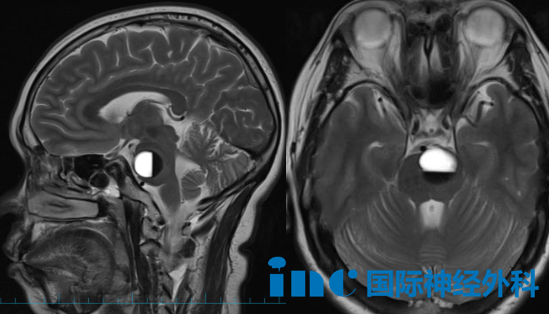

第一位患者是53岁的何女士。原本她以为手术不必急于一时,没想到在面诊巴教授后不到一个月,病灶就在短期内迅速增大并再次出血,症状也从起初轻微的麻木、头晕,快速演变为四肢无力和言语不清。巴教授在评估后表示:"如果选择保守治疗而不做手术,症状持续加重后最严重的后果是什么?我不建议等到大面积出血时才来处理——现在看起来似乎问题不大,但实际上完全可能引发脑干大面积、非常严重的出血。"这台高难度手术在苏州大学附属第四医院进行。巴特朗菲教授主刀,操作区域紧邻面听神经、三叉神经及岩静脉等重要神经血管结构。手术全程在电生理监测下精细操作,最终顺利将病灶完整摘除。目前患者状态平稳,次日即可从ICU转至普通病房。

2026年2月影像

2026年4月影像